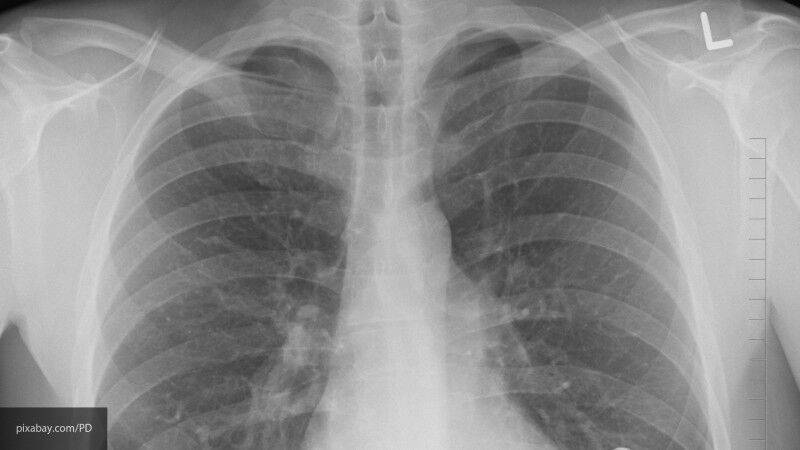

Как изменяются легкие у пациентов, умерших от СOVID-19 — исследование ученых

Международная группа исследователей изучила образцы тканей легких, полученные после вскрытия семи пациентов, умерших из-за коронавируса. Их сравнили с материалами больных, скончавшихся в результате острого респираторного дистресс-симптома, который проявляется при гриппе.

Исследование показало, что в легких пациентов с подтвержденным COVID-19 имеются определенные изменения, которые могут стать причиной многих тяжелых осложнений. Так, специалисты выявили в материалах признаки прогрессивных